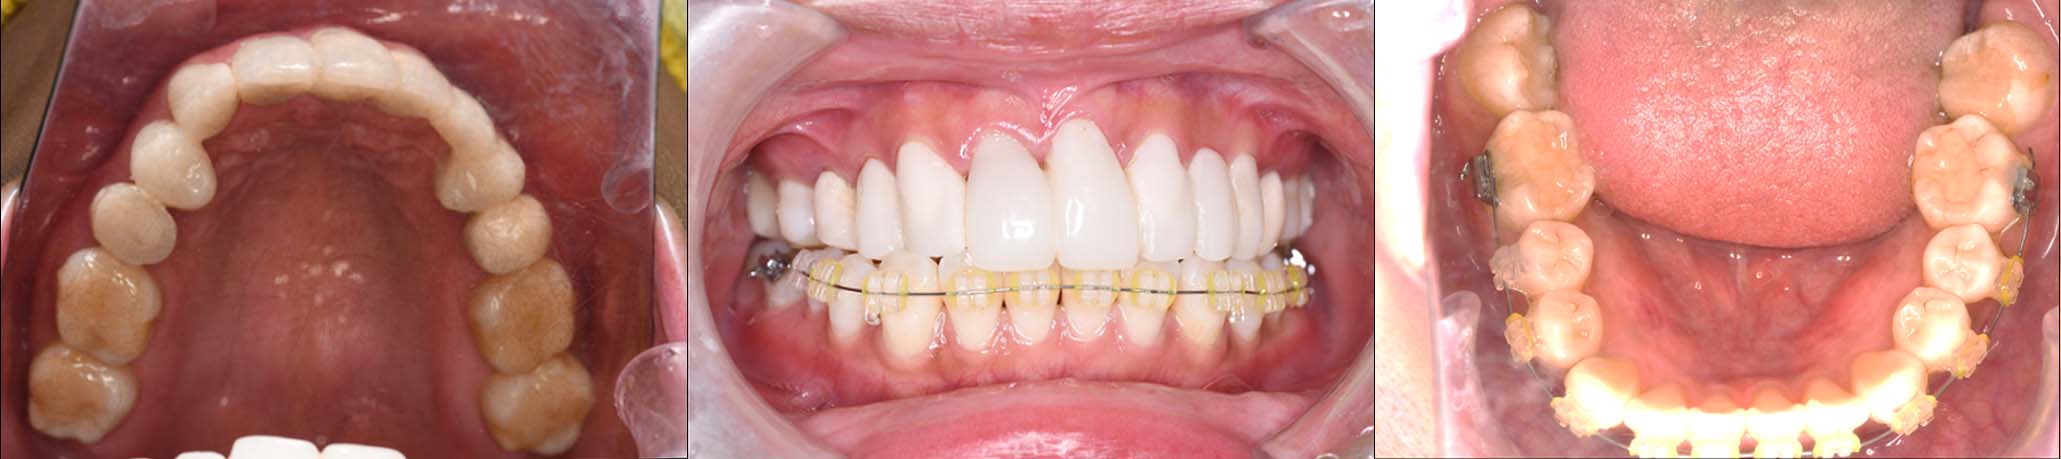

2024年 10月 下顎MTM開始

1月9日

1月30日

2月20日

3月13日

4月24日

9月25日